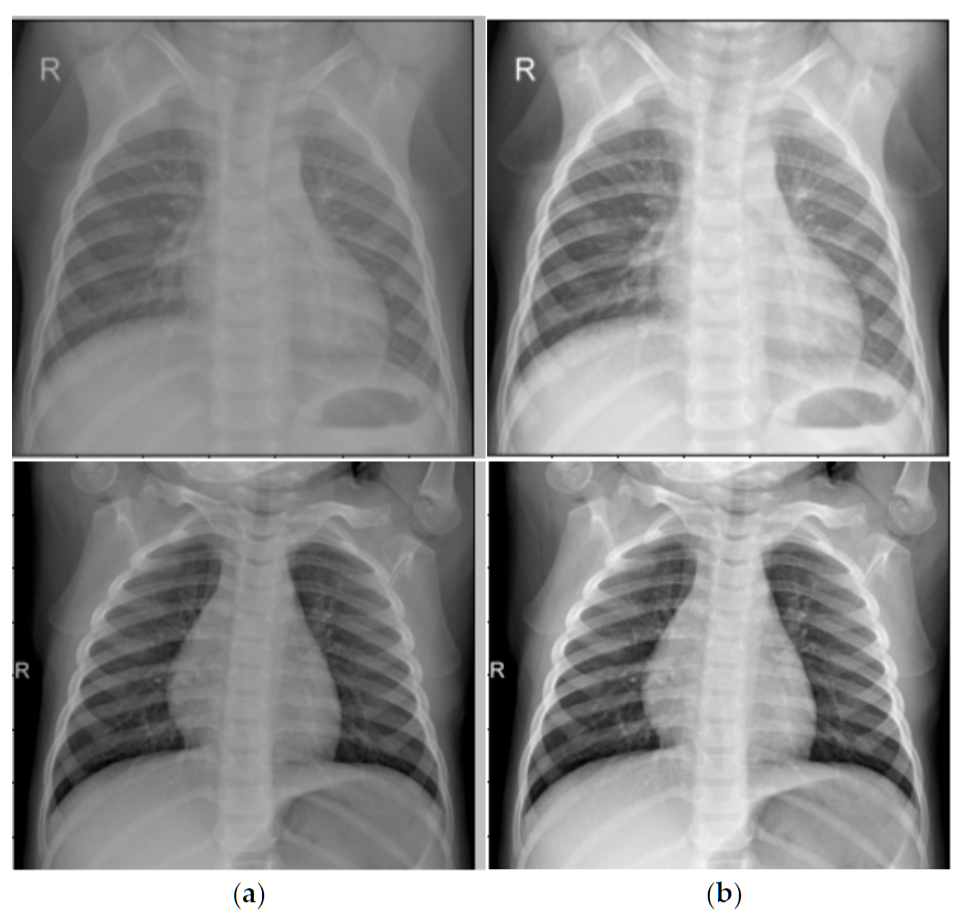

CLAHE对比度增强

CLAHE算法原理

CLAHE(Contrast Limited Adaptive Histogram Equalization)是改进的自适应直方图均衡化:

- 分块处理:将图像划分为小块(如8×8)

- 局部直方图均衡化:对每个块独立进行直方图均衡化

- 对比度限制:限制直方图峰值,避免噪声放大

- 双线性插值:块边界使用双线性插值平滑过渡

CLAHE增强前后对比:左图为原始胸片,右图为CLAHE增强后

不同CLAHE参数的效果对比,从弱增强到最强增强的渐进效果

CLAHE增强效果定量评估:

- 对比度提升倍数:1.05

- 动态范围扩展倍数:1.33

- 信息量提升倍数:1.14

- 边缘强度提升倍数:18.19

- PSNR:28.05 dB,SSIM:0.566

CLAHE增强的详细分析,包括边缘检测、强度分布和增强效果评估